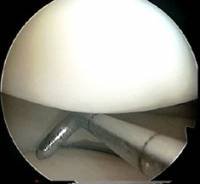

The first part of any arthroscopy should involve only the arthroscope and the blunt probe. Too many surgeons fail to fully explore the joint with the probe before dealing with any abnormality found inside. On the left, you can see the probe being used to explore under the meniscus.